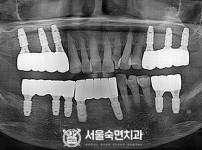

임플란트-전후사진4